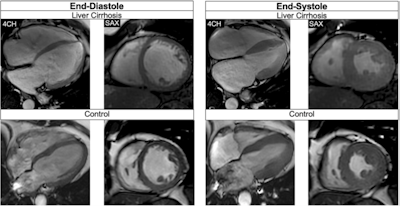

Balanced steady-state free precession cine-images at end-diastole and end-systole (4-chamber (4CH) and midventricular short axis (SAX) views) of a 51-year-old male patient with liver cirrhosis due to primary sclerosing cholangitis (MELD score: 16 points, Child-Pugh class B) and of a 53-year-old male control. The patient showed a higher LVEDVi (108.3 versus 71.8 mL/m2)/RVEDVi (112.1 versus 67.5 mL/m2), a higher LVEF (73.0 versus 64.0%)/RVEF (60.5 versus 57.0%), and increased biventricular strain (LVGLS: −26.0%, LVGRS: 39.9%, LVGCS: −20.4%, RVGLS: −22.9%, RVGRS: 12.3%, RVGCS: −8.0%) than the age-matched control (LVGLS: −14.0%, LVGRS: 19.0%, LVGCS: −17.0%, RVGLS: −22.8%, RVGRS: 13.3%, RVGCS; −7.3%). Furthermore, the patient showed an elevated ECV (32.0%) compared to the control (22.4%).All figures courtesy of Dr. Jennifer Erley et al and European Radiology.